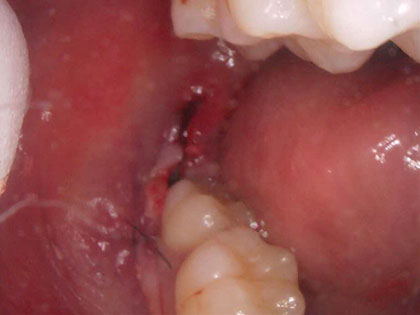

• 抜歯後の写真がこちら

• 親知らずの抜歯治療中1

• CTでもかなり近くシビアなケースです。歯肉を切開し、粘膜を開き親知らず周辺の骨を削り、頭の部分と根っこの部分に分け抜歯しました。

• 抜歯した部分を洗浄し、糸で縫いました。